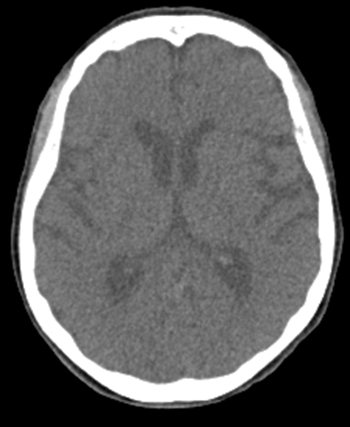

this image is an example of axial PET, CT or fused

axial PET

CT axial

axial fused